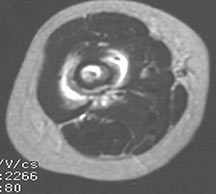

- May arise from any bone and any site within a bone (epiphyseal, metaphyseal, diaphyseal)

- Radiographically variable appearance: may appear benign (geographic) or malignant (permeative or moth eaten)

- Pain and soft tissue swelling

- Femur